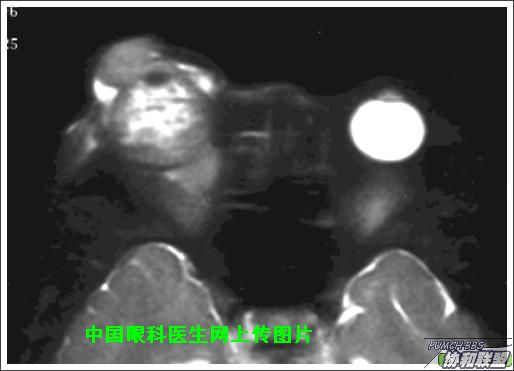

出院后半年发现右眼出现肿物,增长较快,随来京再次就诊(图1),转来我科。门诊检查发现:右眼无光感,结膜下肿物,突出睑裂。眼球突出,上移位。眶外侧可触及硬性肿物。超声(图2),CT(图3),MRI(图4,5,6)显示如图.